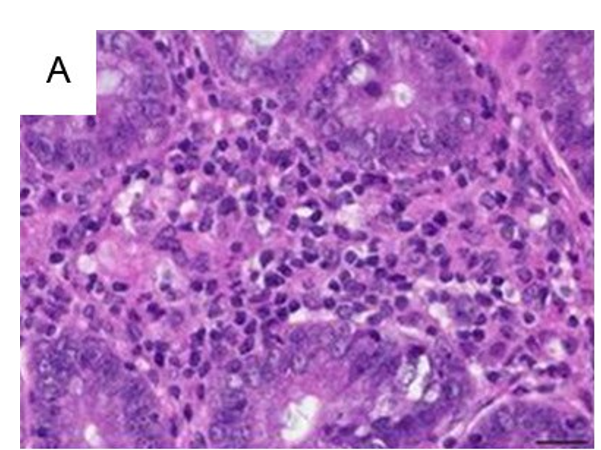

组织病理

Histological Pathology

小鼠肠道炎症模型的组织病理学(一)

小鼠肠道炎症模型的组织病理学(二)

小鼠肠道炎症模型的组织病理学(三)